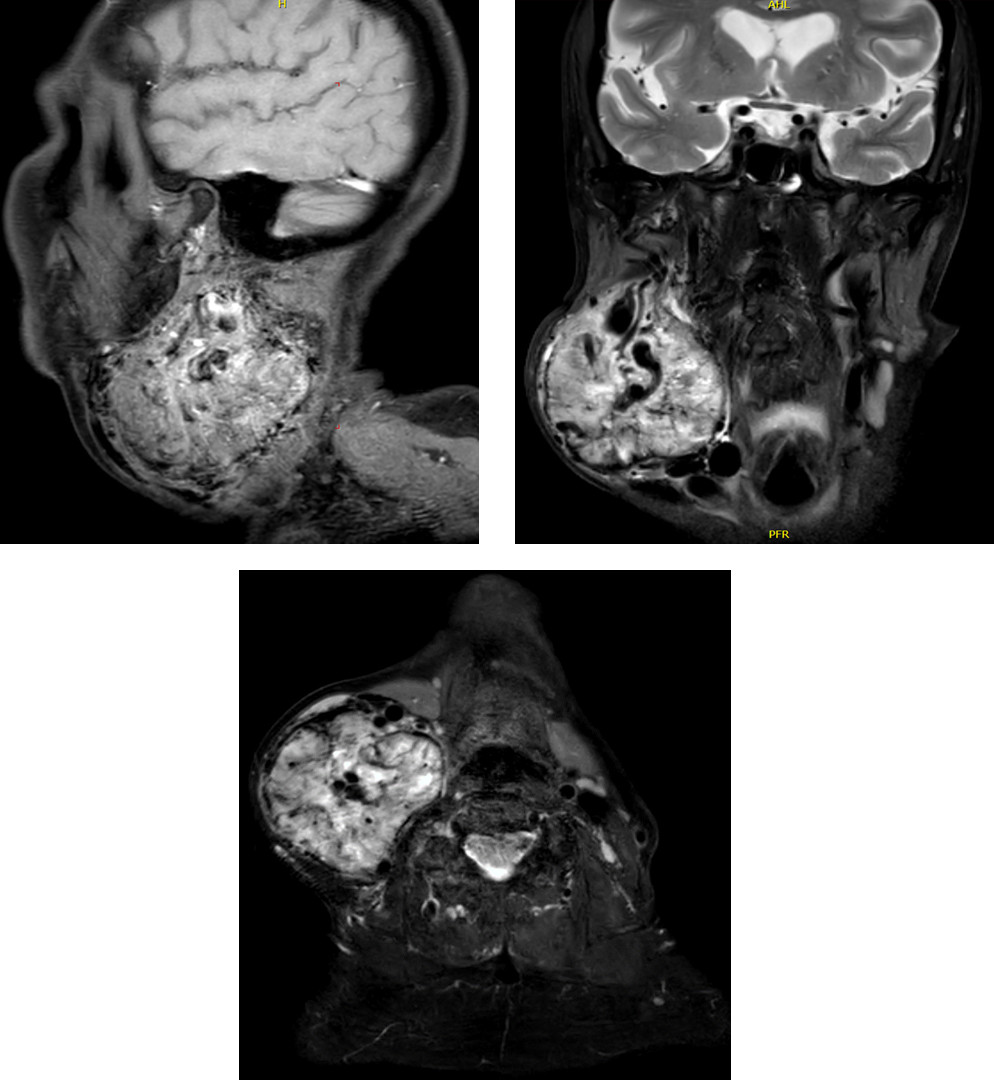

A 74-year-old female was on observation for an asymptomatic vagal paraganglioma for several years, until she desired to undergo surgery. At the time of surgery, the tumor was 7cm and the nerve was already paralyzed.

It was treated surgically on June 2025 with complete tumor resection and type I thyroplasty. Surgery led to worsening of the X cn paralysis with severe dysphagia and aspirations. Patient is currently fed through PEG.